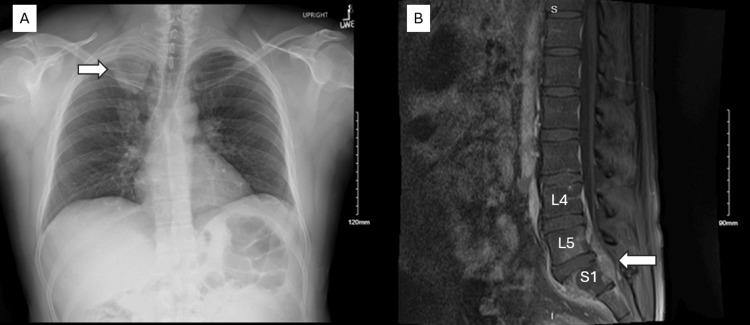

Thoracic SMARCA4-deficient undifferentiated tumor (TSDUT) is a rare and quite new classification of primary pulmonary malignancy. It is classified as a non-small cell lung cancer, typically associated with smoking, and is highly aggressive. Its clinical features, immunohistochemistry, and pathology are quite unique. In this case report, we describe the clinical course of TSDUT pancoast tumor in a 40-year-old male, without a substantial smoking history, but a significant history of occupational welding.

胸段SMARCA4缺陷型未分化肿瘤(TSDUT)是原发性肺恶性肿瘤中一种罕见且较新的分类。它被归类为非小细胞肺癌,通常与吸烟有关,且具有高度侵袭性。其临床特征、免疫组化和病理学都相当独特。在本病例报告中,我们描述了一名40岁男性TSDUT潘科斯特瘤的临床病程,该患者无大量吸烟史,但有显著的职业焊接史。